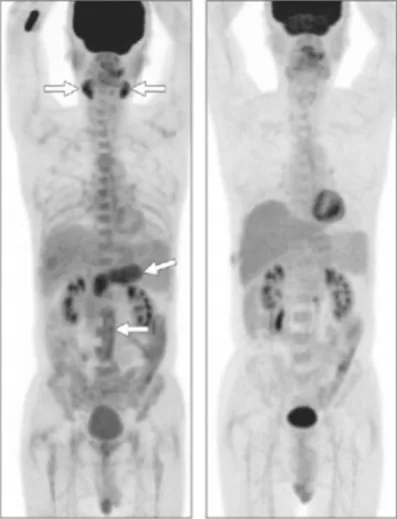

La TEP-FDG montre une hyperfixation pancréatique dans la PAI comme dans l’adénocarcinome pancréatique [26]. Cependant l’aspect de la fixation est évocateur de la PAI lorsqu’il est pan-glandulaire ou bien multifocal (Fig. 15), et/ou s’associe à une ou des fixations extra-pancréatiques [26].

Figure 15. Aspect PET-FDG caractéristique de PAI à IgG4. Noter la fixation des 2 glandes salivaires (Sd de Mikulicz), la fixation péri-aortique abdominale témoignant de la fibrose rétropéritonéale et la fixation diffuse de la glande pancréatique